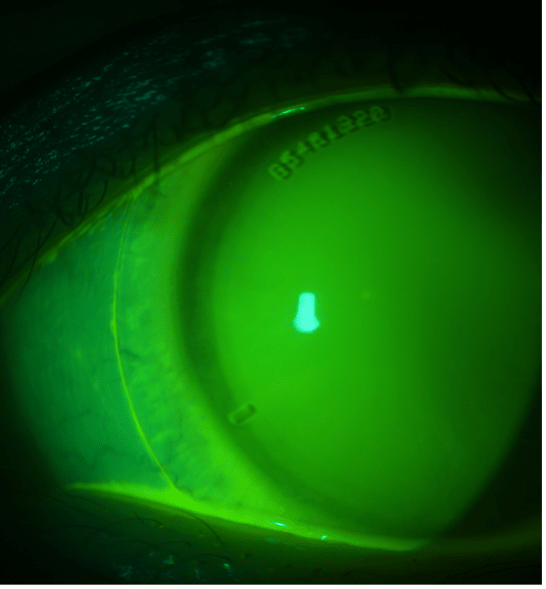

A 25-year-old female presented for a scleral lens follow-up. She had been fitted in scleral lenses 6 weeks prior for correction of refractive error. She reported no significant issues with vision at follow-up, just mild dryness as the day went on. After lens removal, upon slit lamp examination, the below was observed. What is your diagnosis? How would you resolve this finding?

The patient was found to have peripheral corneal epithelial bullae nearly 360º around in both eyes. Evaluation with the scleral lenses on eye demonstrated that the lens was landing on the peripheral cornea just inside the limbus. The rings of bullae therefore are mechanical in nature and not from hypoxia. This is apparent when you observe the contact lens fit with fluorescein (Figure 2).